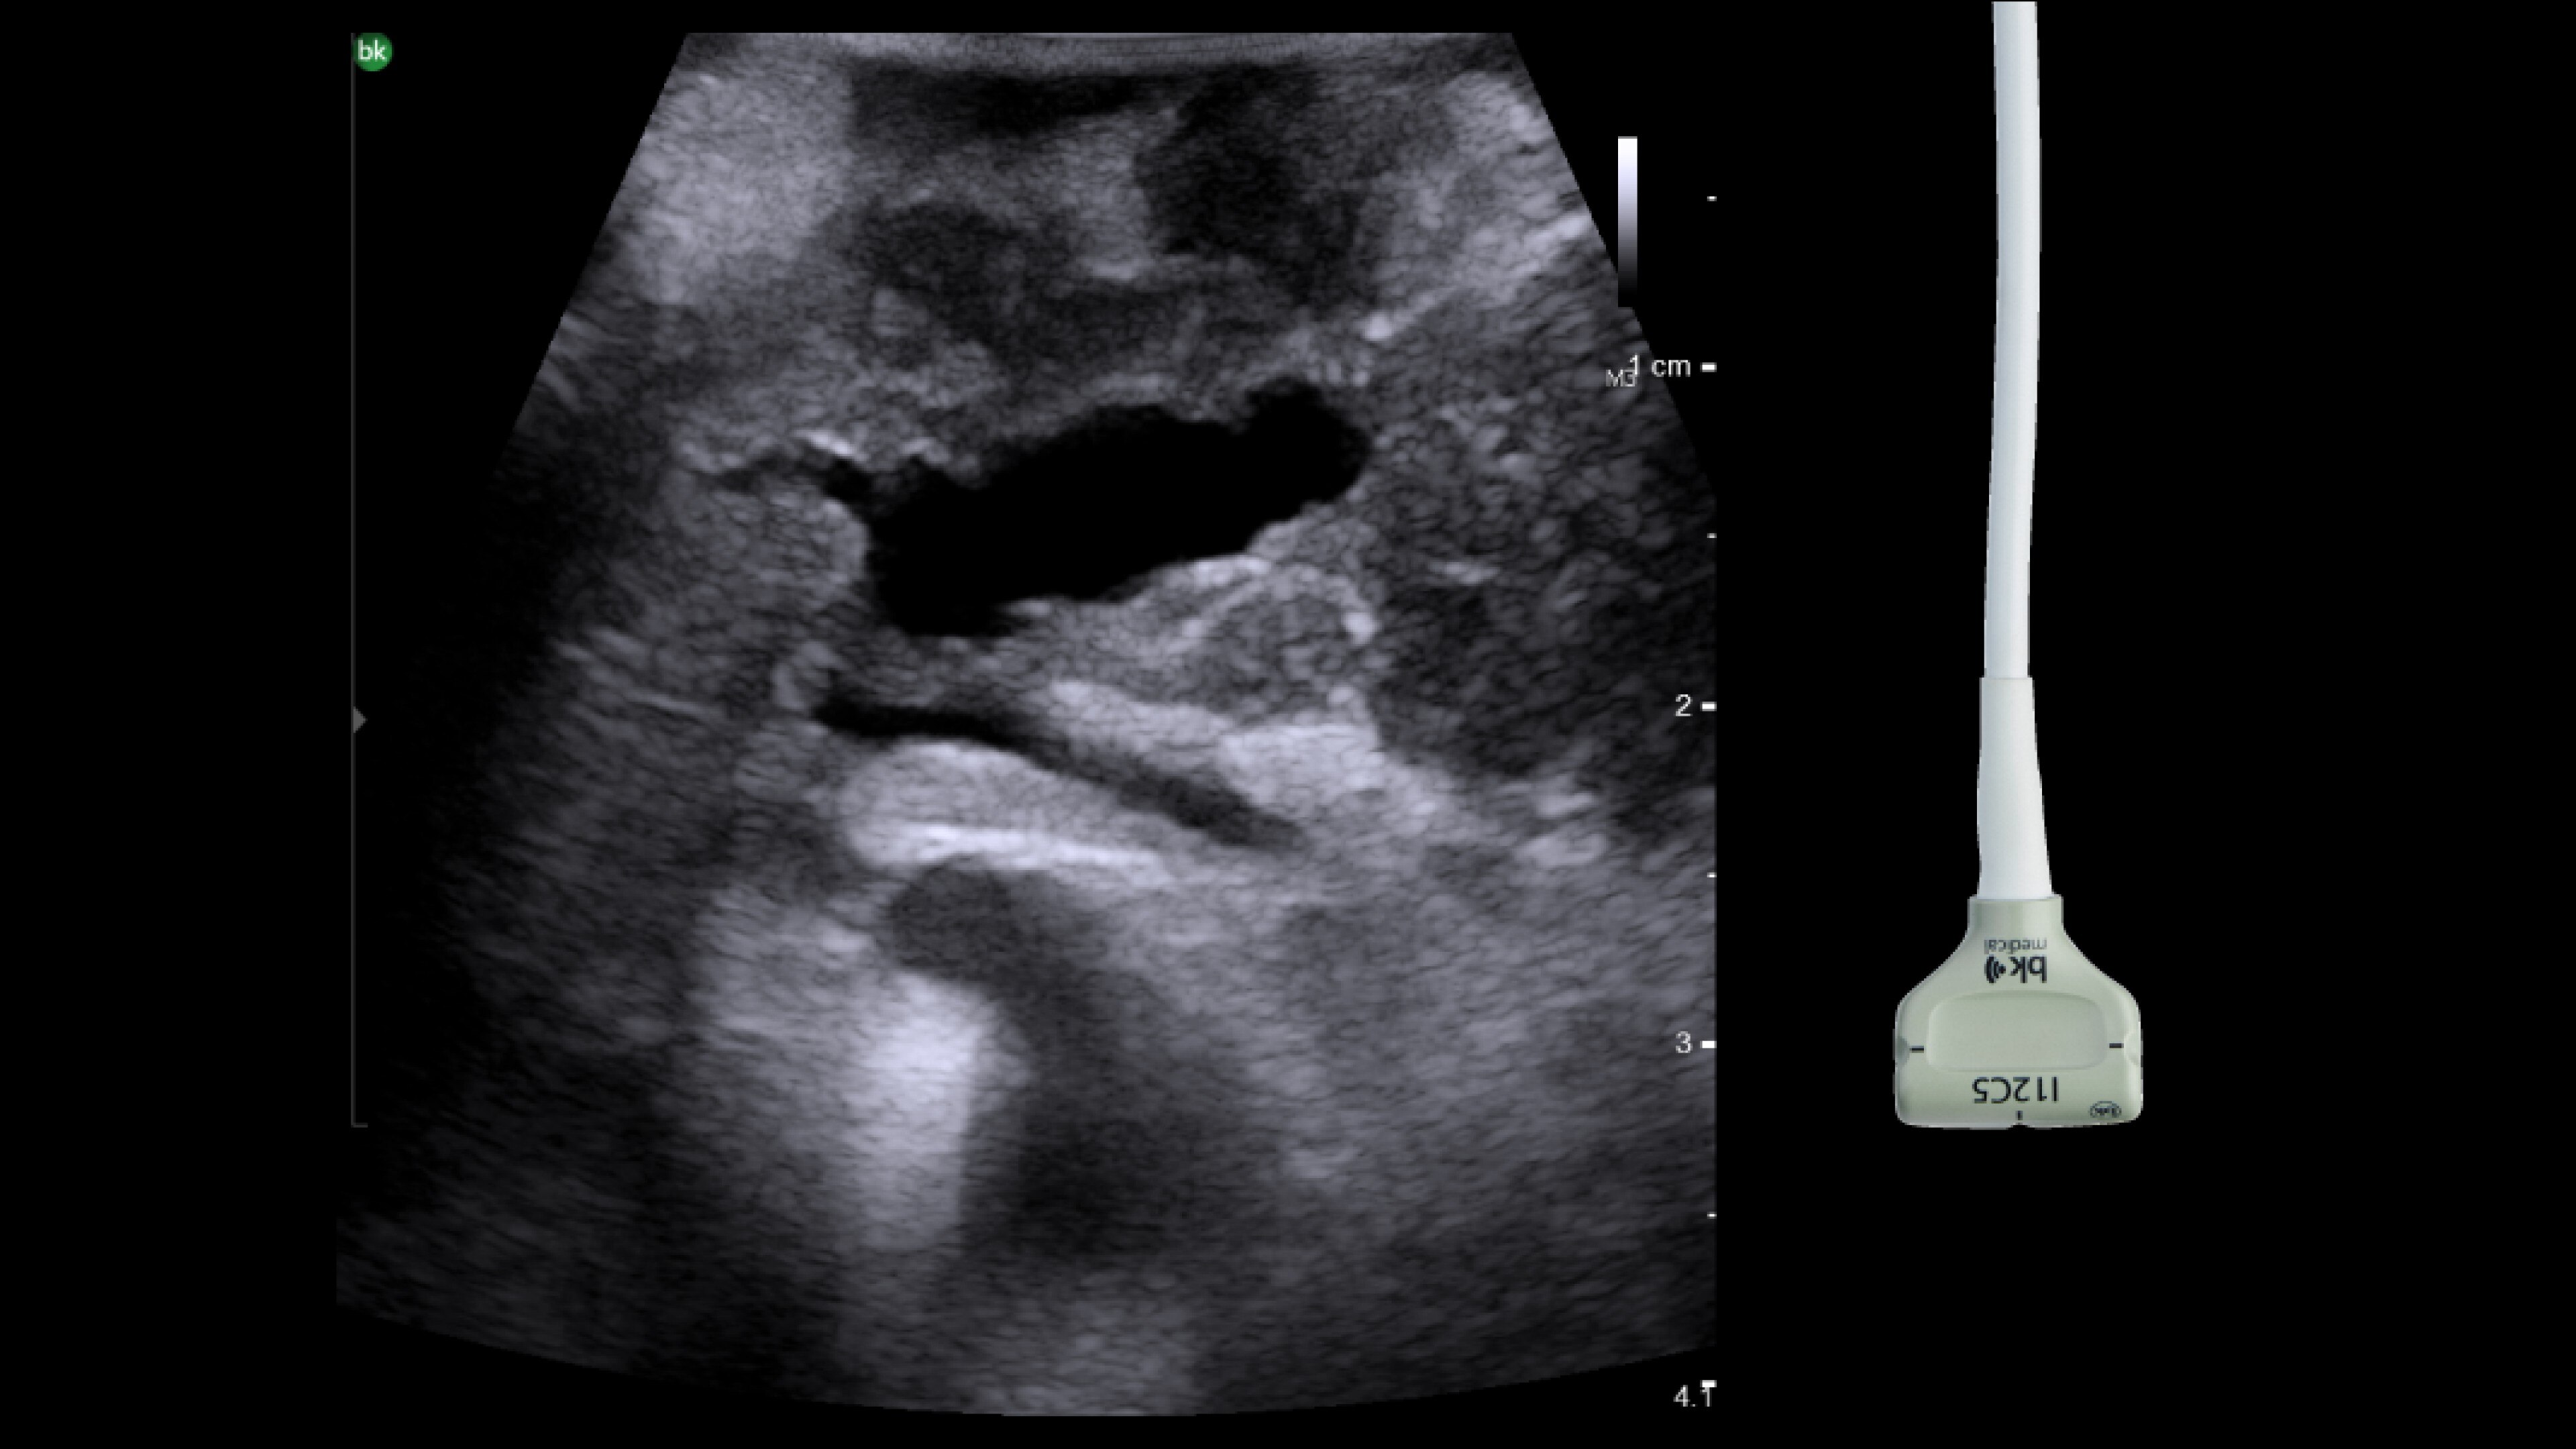

Active imaging with intraoperative ultrasound supports critical decision-making in open or minimally invasive tumor resections.

• Enable visualization of disease staging at the time of surgery with excellent image quality.

• Visualize complex anatomical variations and identify tumor location.

• Define adequate margins of resection.

• Guide and view needle placements.

• Assess surgical planning and check for vessel patency at the end of the procedure.

Read case study: Use of ultrasound during two stage laparoscopic liver resection.